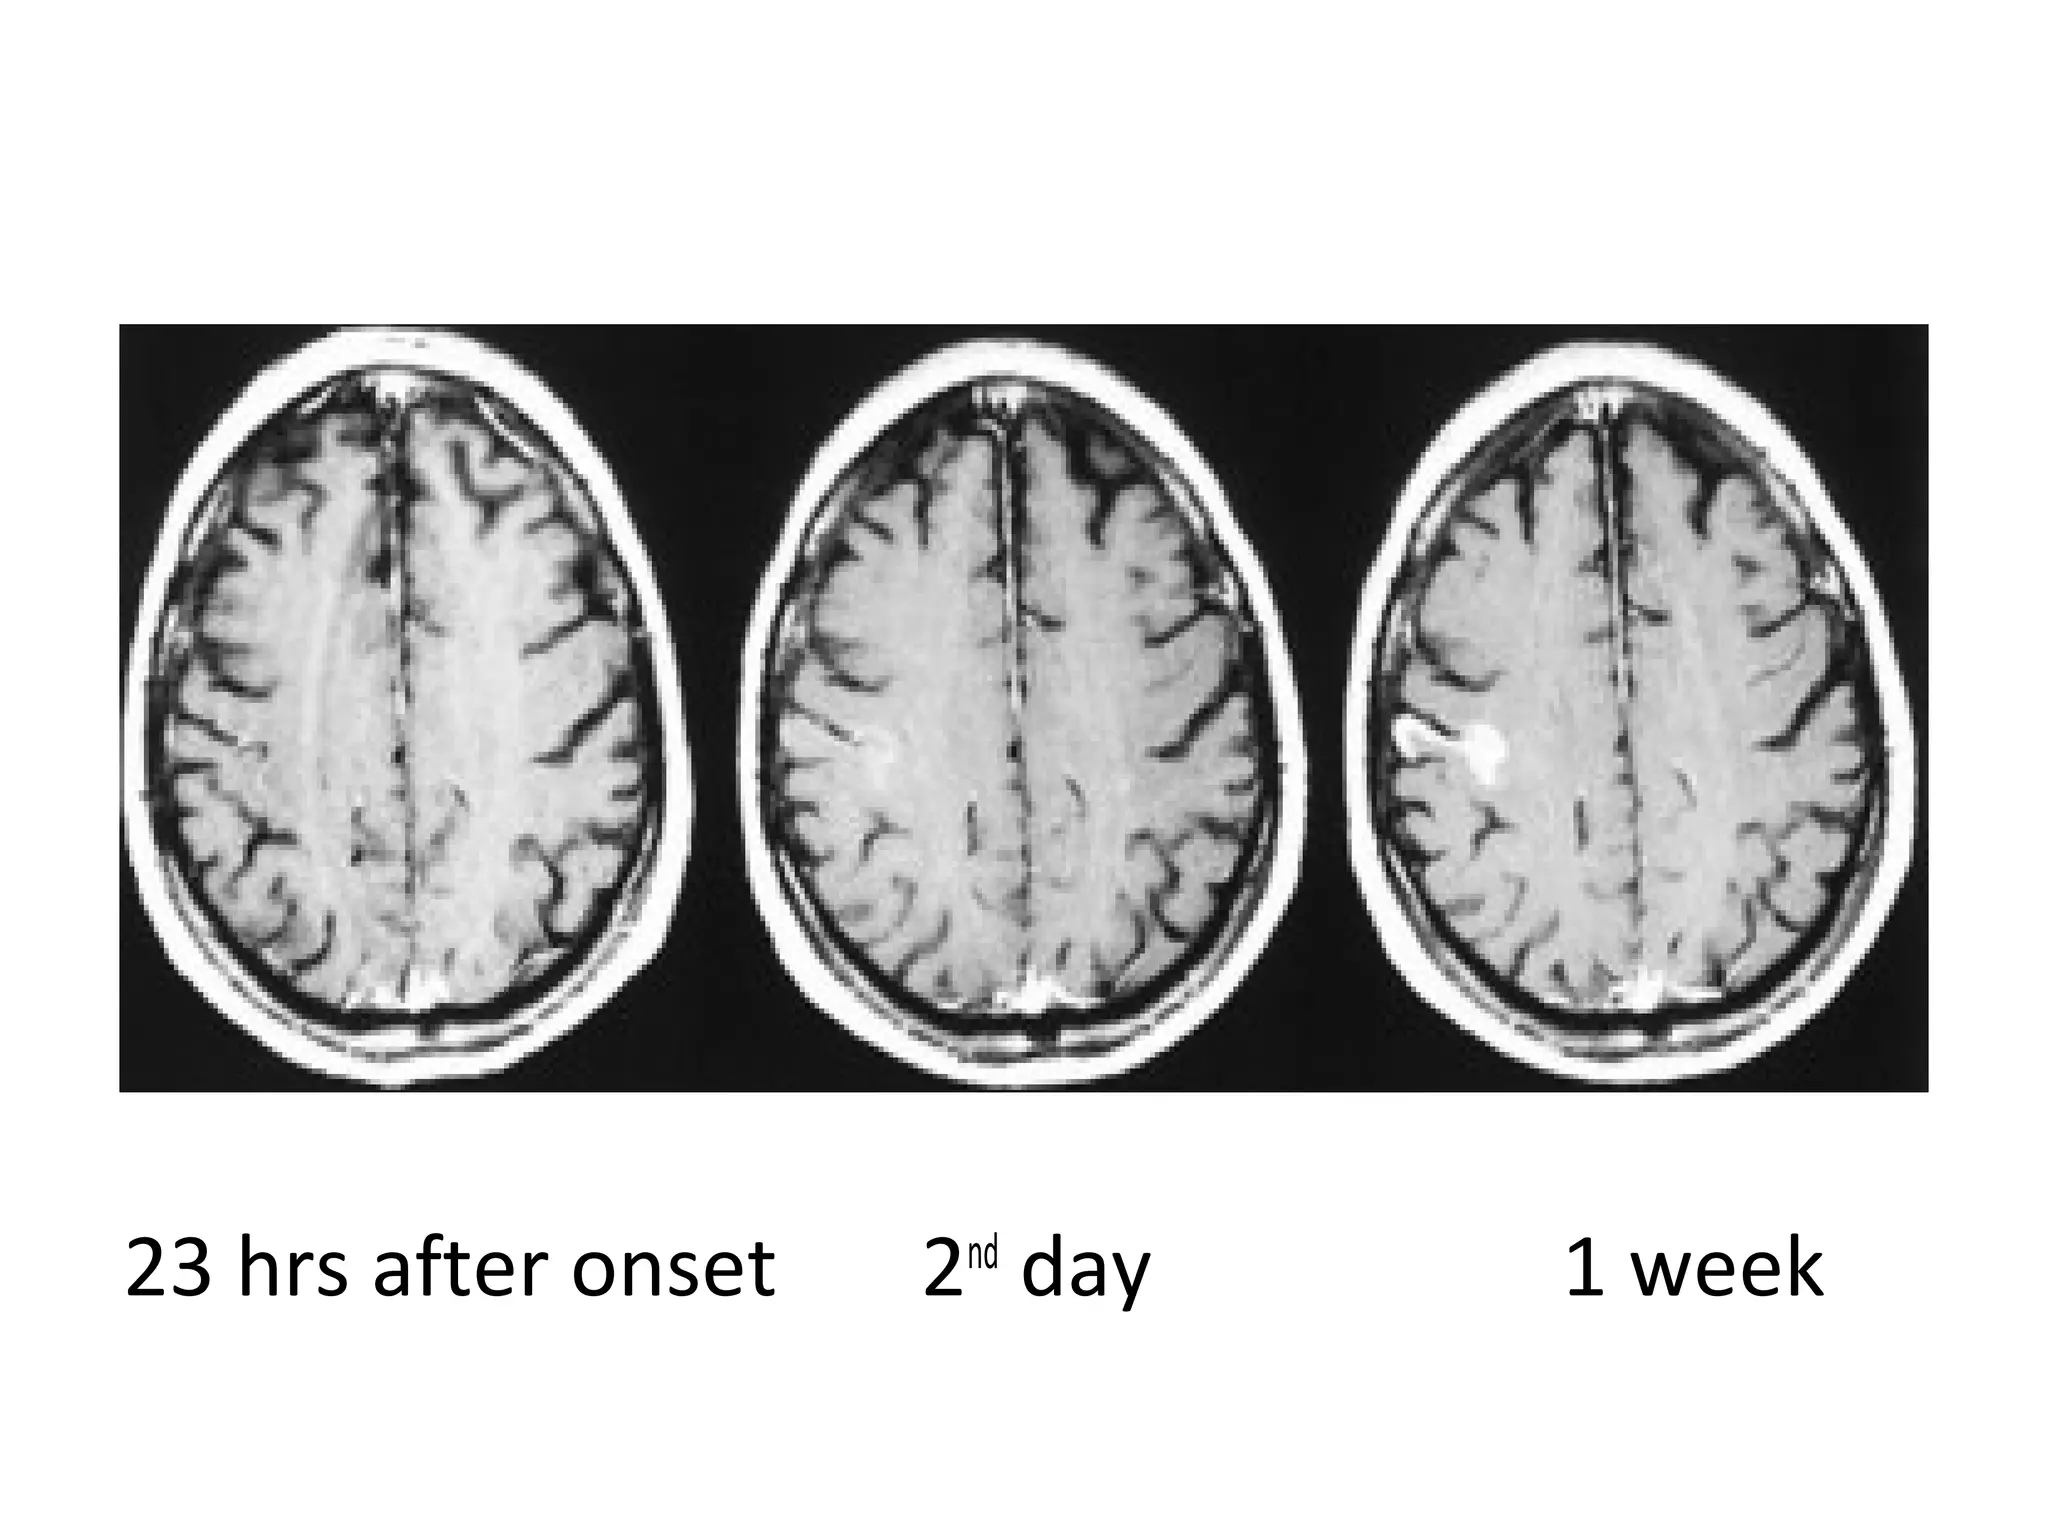

8 hrs after onset 2nd

23 hrs after onset 2nd

day 1 week